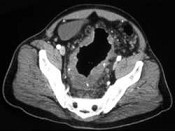

- 单项选择题男,15岁, 下腹疼痛不适,结合图像, 最可能的诊断是 ( )

A、结肠和系膜多发性血管瘤

B、结肠癌腹腔淋巴结转移

C、结肠淋巴瘤

D、假膜性肠炎

E、结肠溃疡性结肠炎